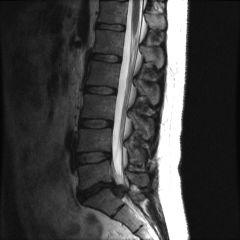

Disc Herniation

A disc herniation can be one of the most painful and debilitating conditions that any person can experience. It is caused when tears in the outer fibrous part of the intervertebral disc, allows the jelly like substance within it, known as nucleus pulposes, to escape. When the disc has herniated, the nucleus pulposes is free to wreck havock on neighbouring nerves and can cause syptoms such as sciatica. Herniation can occur anywhere in the spine, but are most common in the low back and neck.Symptoms of a herniated disc can vary immensely. They can range from little or no pain if [...]